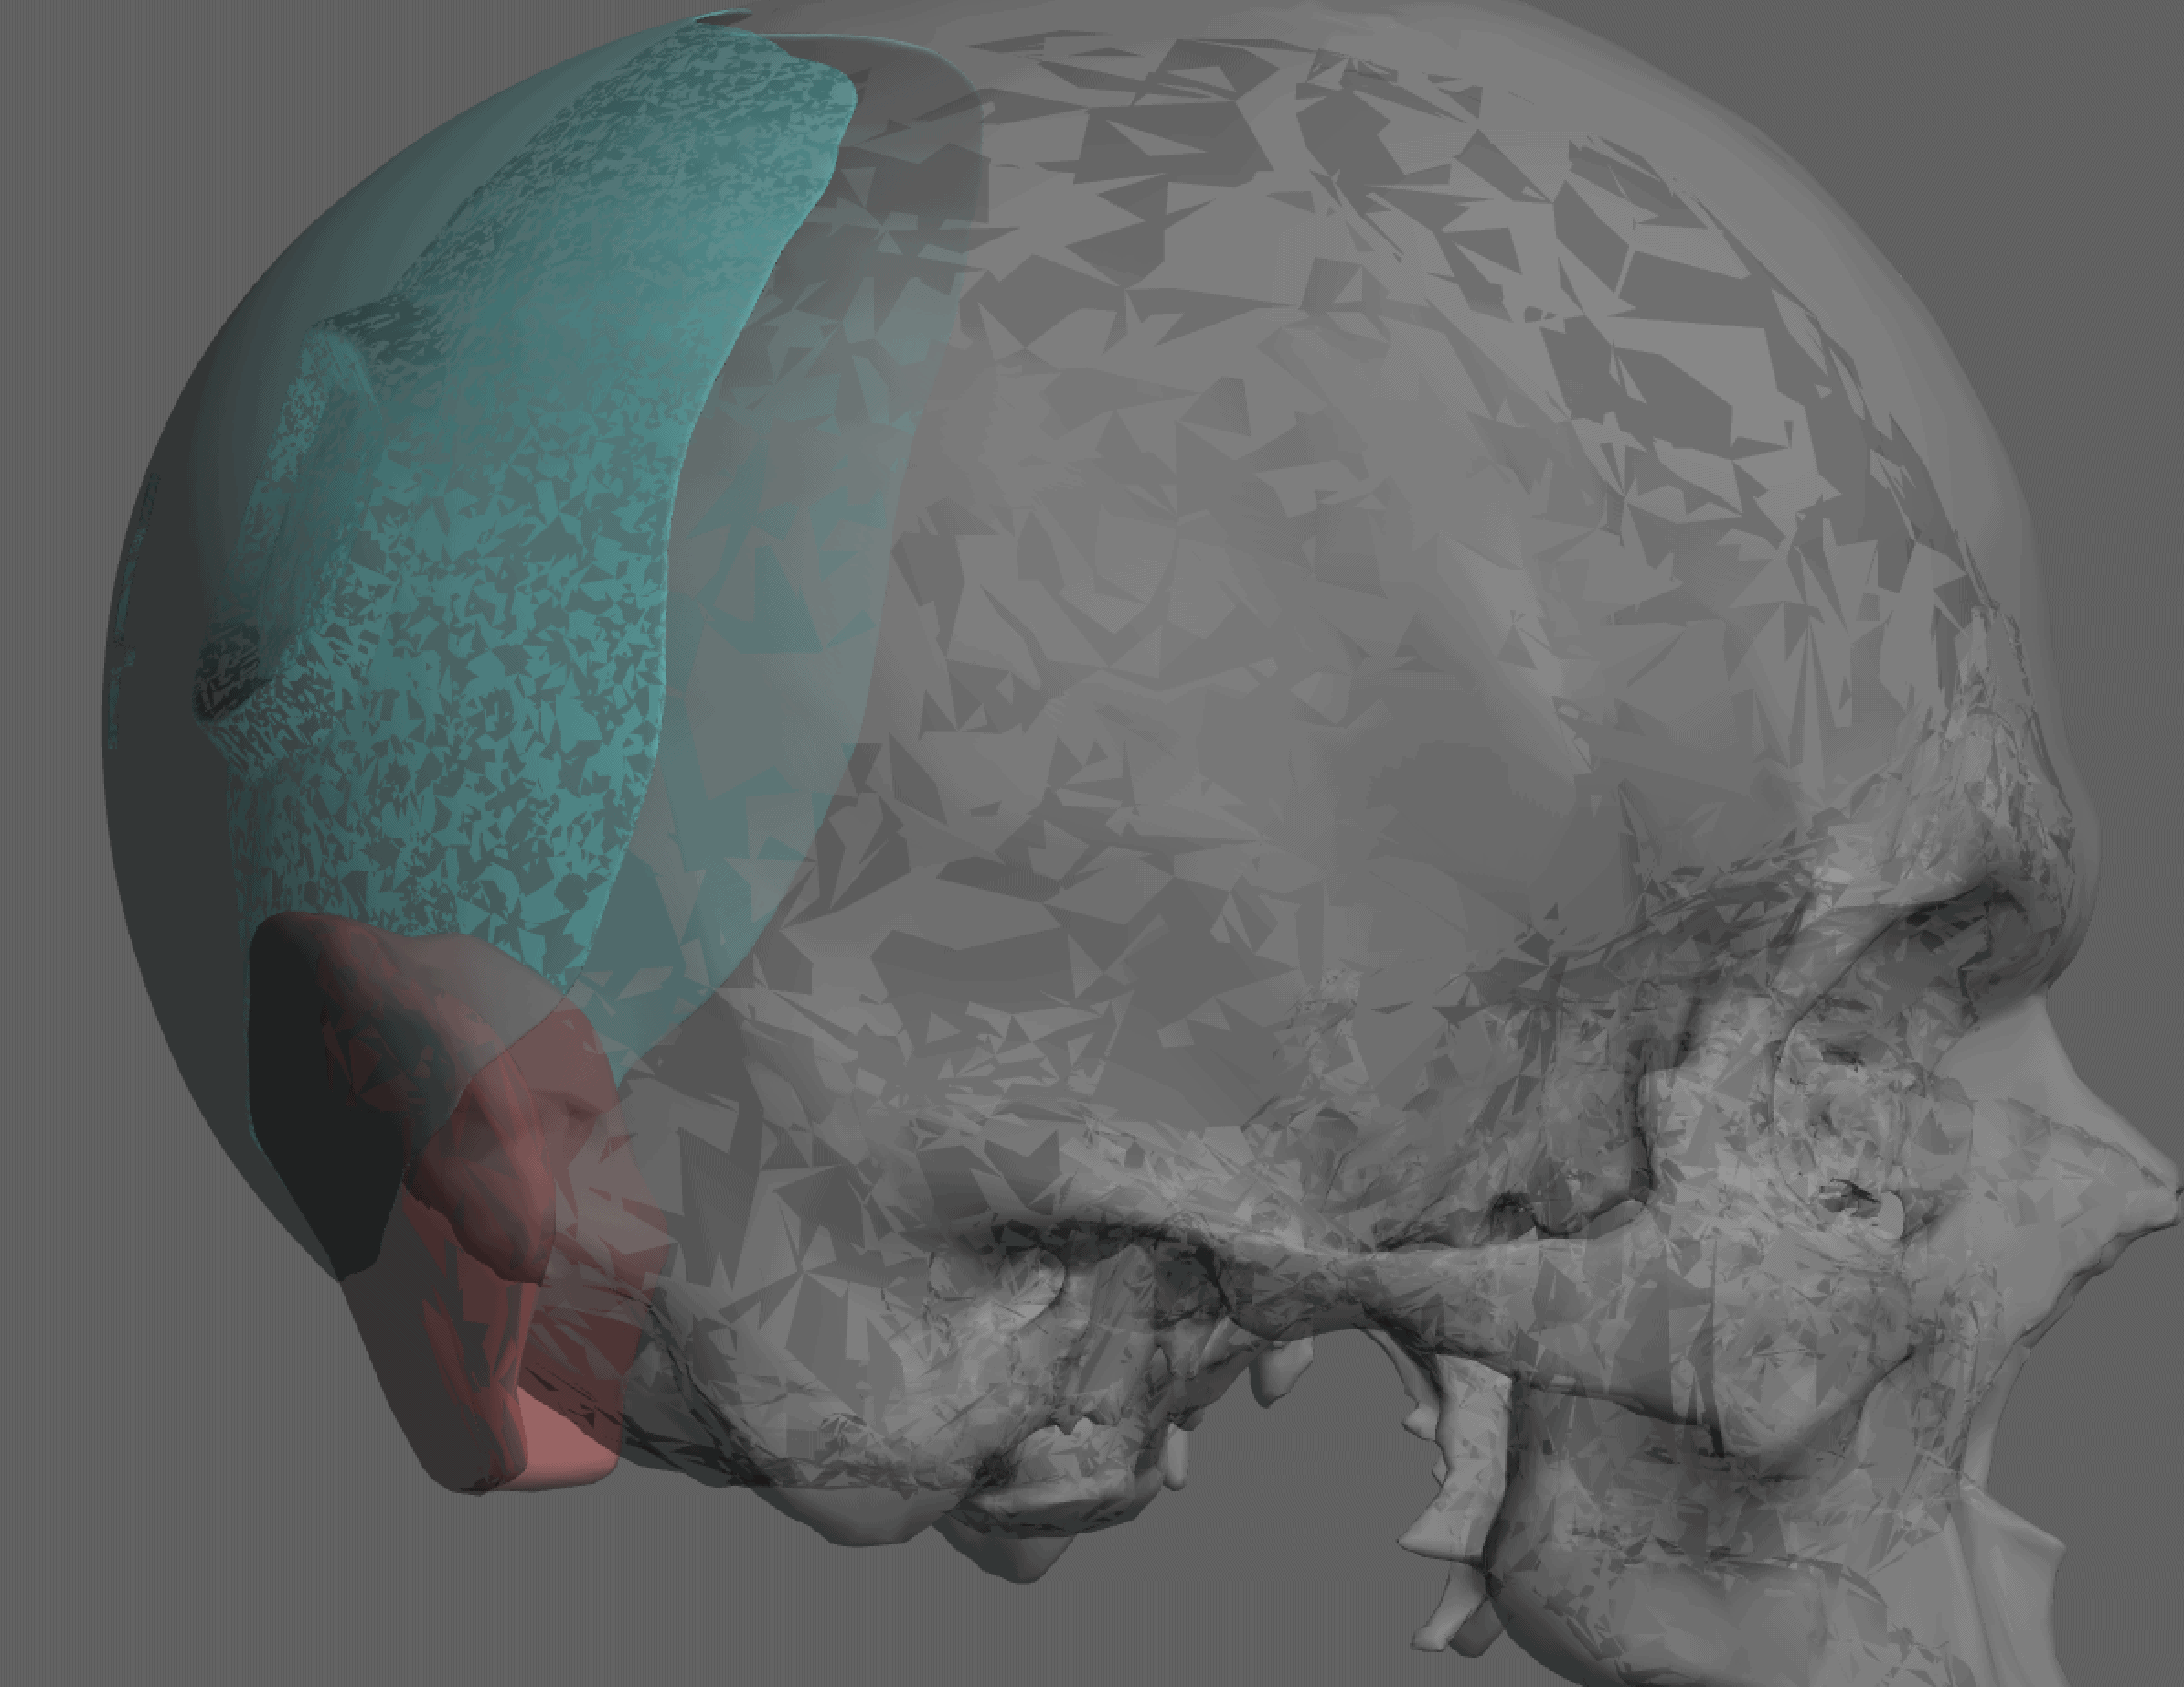

Patient 84

Desire for change of head shape from front view form an inverted V shape to a rounder and wider head shape.

Placement of custom extended forehead-temporal implants through incisions in the crease behind the ear. (he had a prior back of head skull implant which is green in the implant designs and which the head widening implants partially covered it)

Desire for change of head shape from front view form an inverted V shape to a rounder and wider head shape.

Placement of custom extended forehead-temporal implants through incisions in the crease behind the ear. (he had a prior back of head skull implant which is green in the implant designs and which the head widening implants partially covered it)